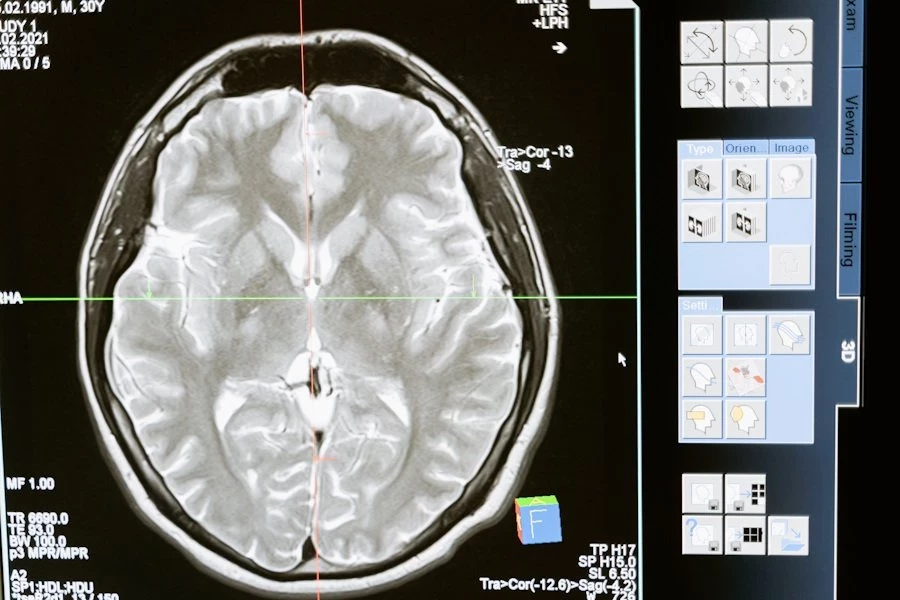

«Ошибки молодости»: алкоголь может ускорить старение мозга

Исследователи выяснили, что чрезмерное употребление алкоголя в молодости может оставлять необратимые последствия в мозге, которые напоминают изменения, характерные для старения. Эти выводы опубликованы на портале Neurobiology of Aging.

После завершения "алкогольного периода" мышей оставили без спиртного до достижения ими возраста от 9 до 12 месяцев — это соответствует 30–40 годам у людей. Когда животных обследовали, выяснилось, что употребление алкоголя в молодом возрасте оставило след в их мозге. Нейронные связи функционировали хуже, что отражалось на передаче сигналов между нервными клетками. Подобные изменения часто сопровождают ухудшение памяти и когнитивных способностей у пожилых людей.